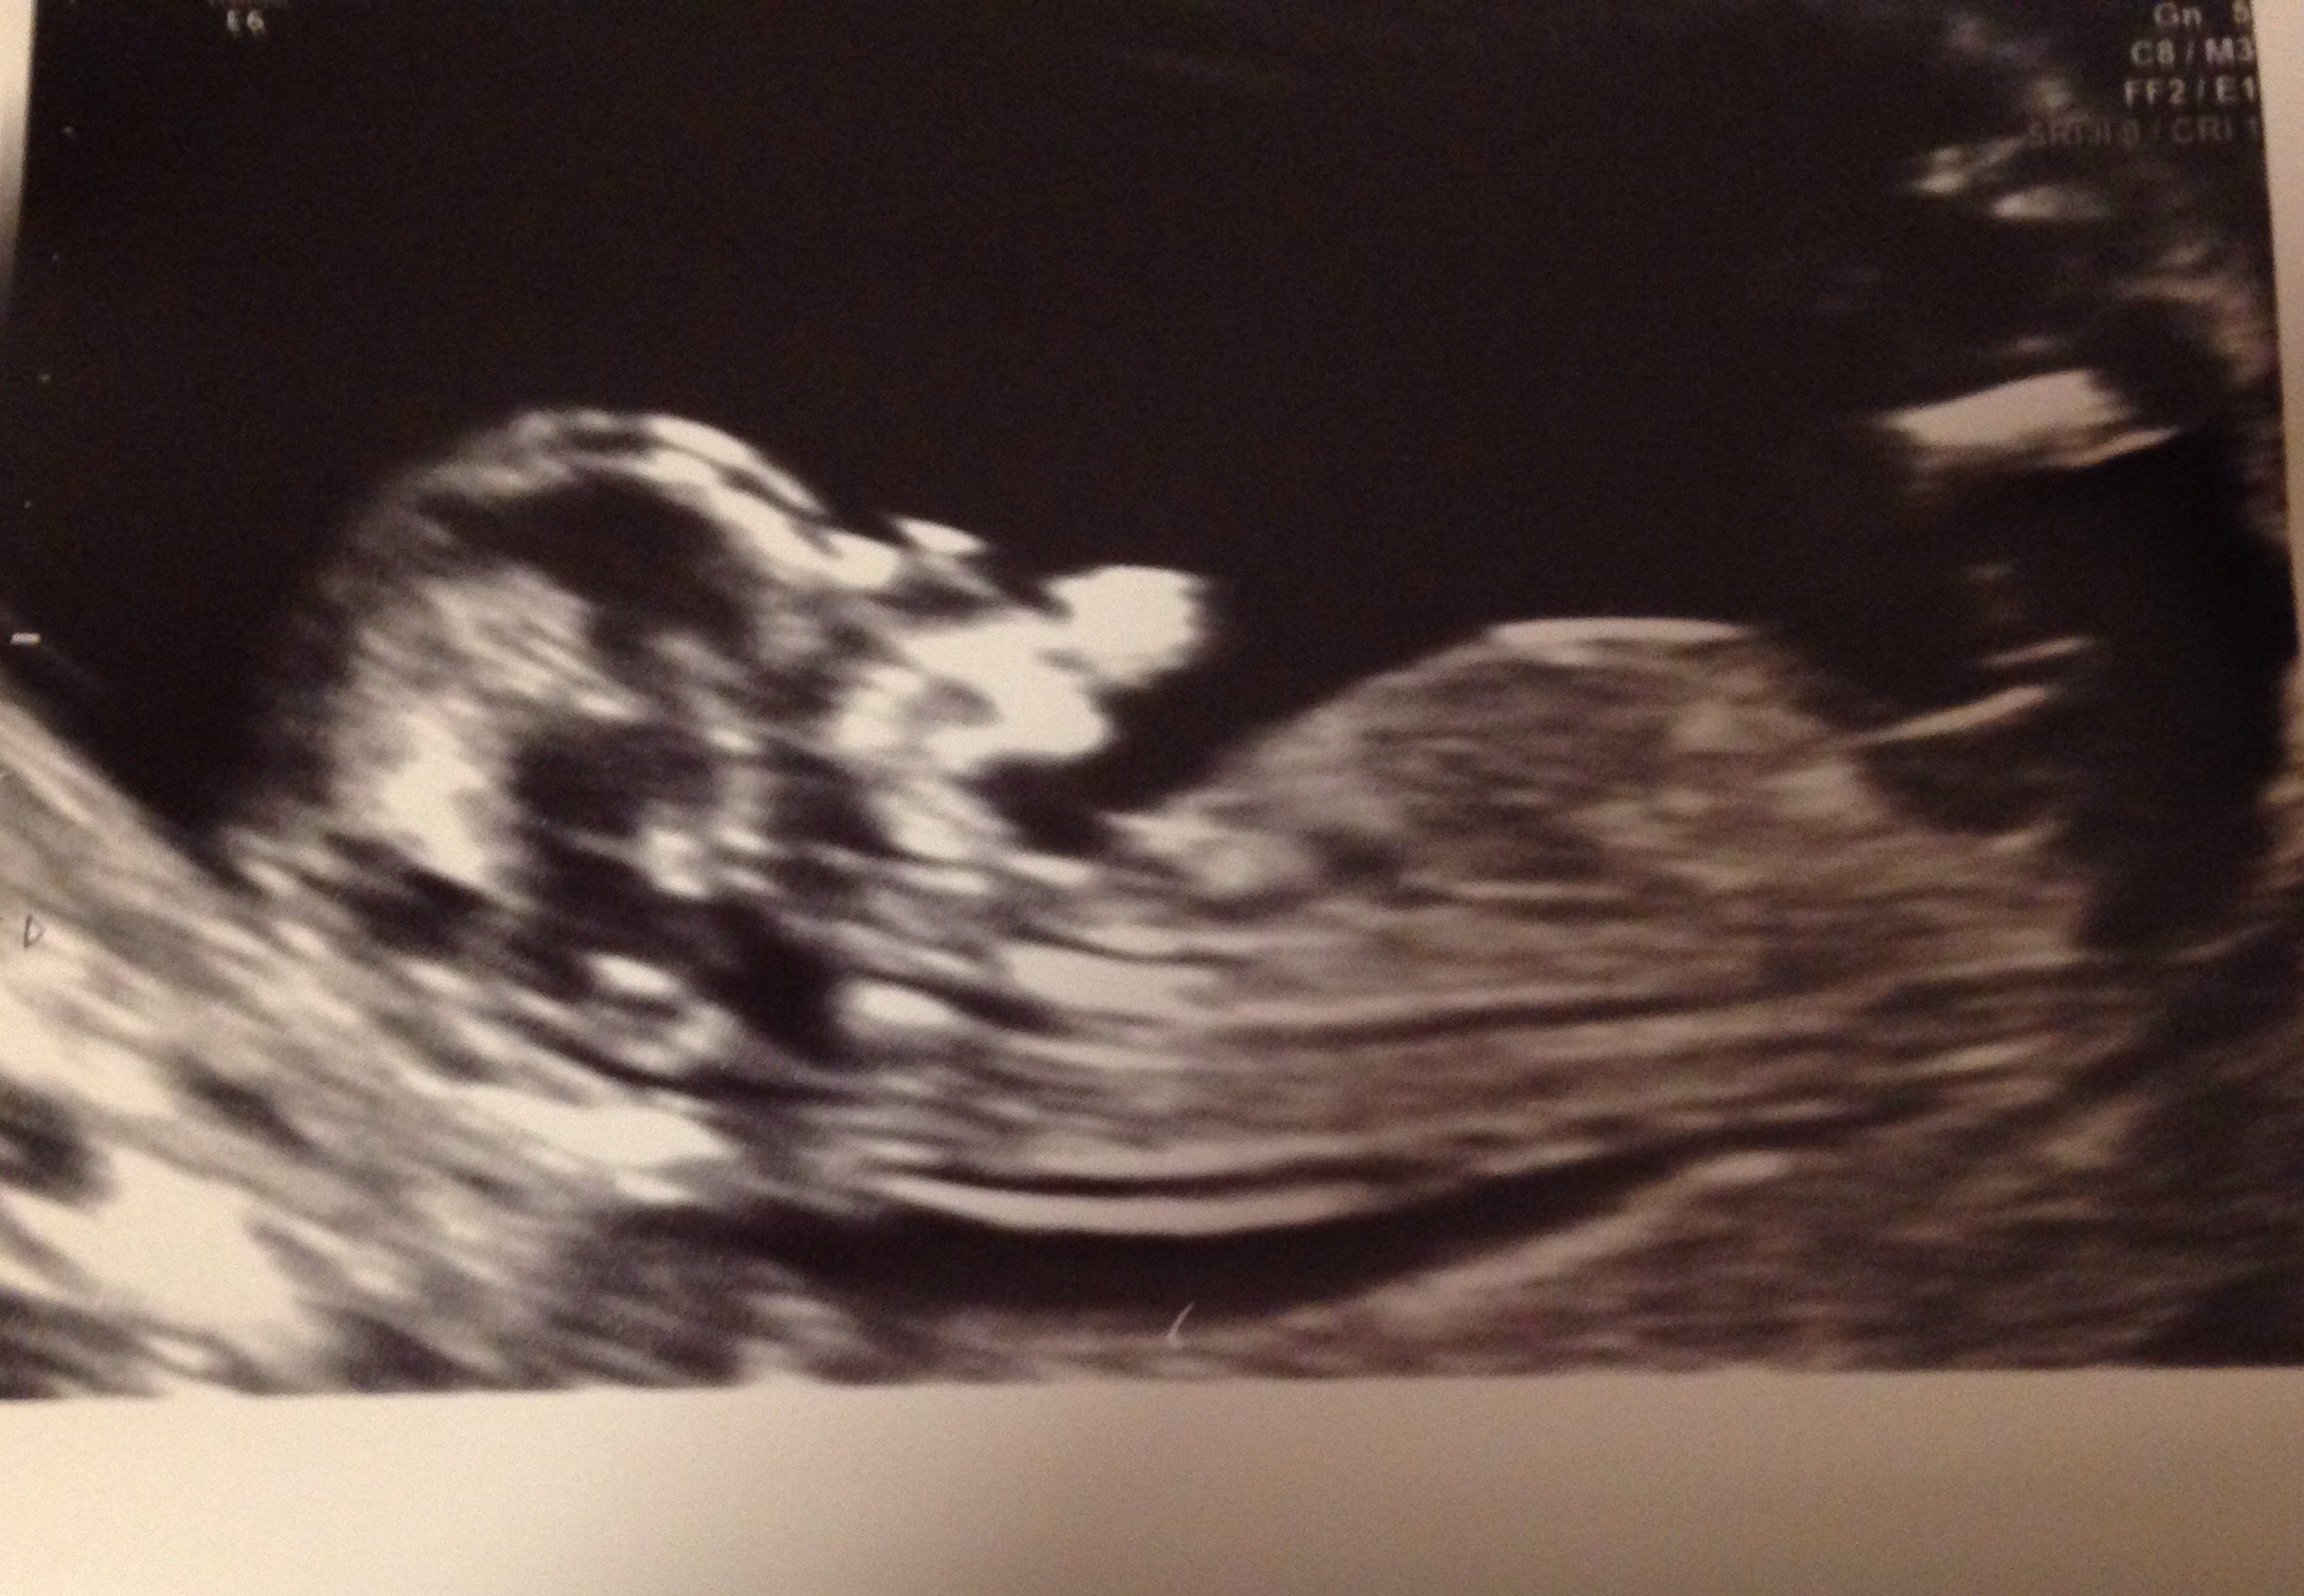

My babies first scan nearly 9 weeks

Attachment 21164